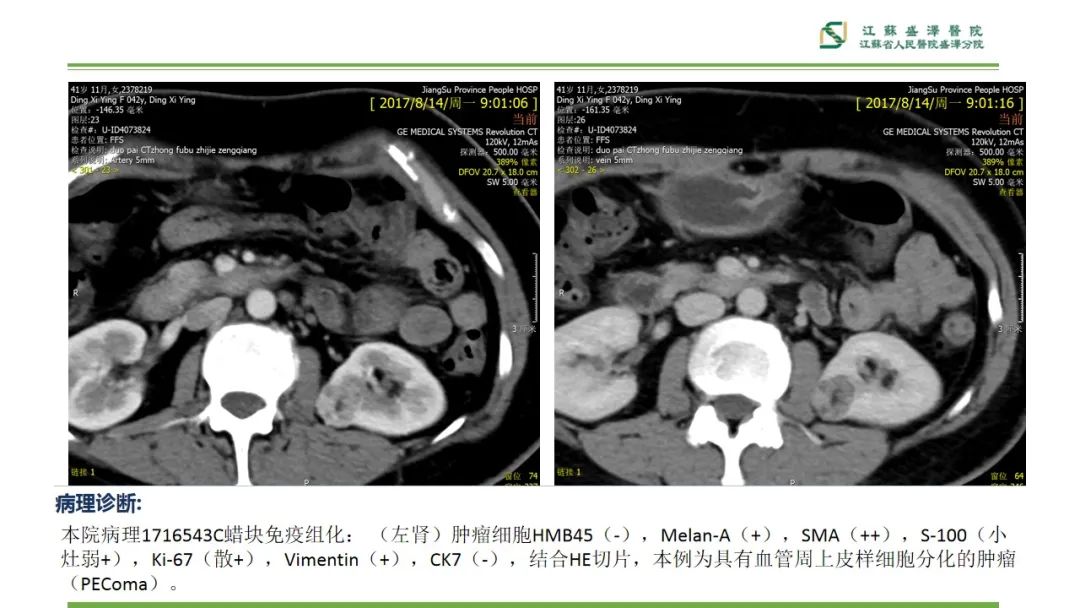

【PPT】肾脏实性肿瘤的良恶性鉴别--影像诊断思路分析-4